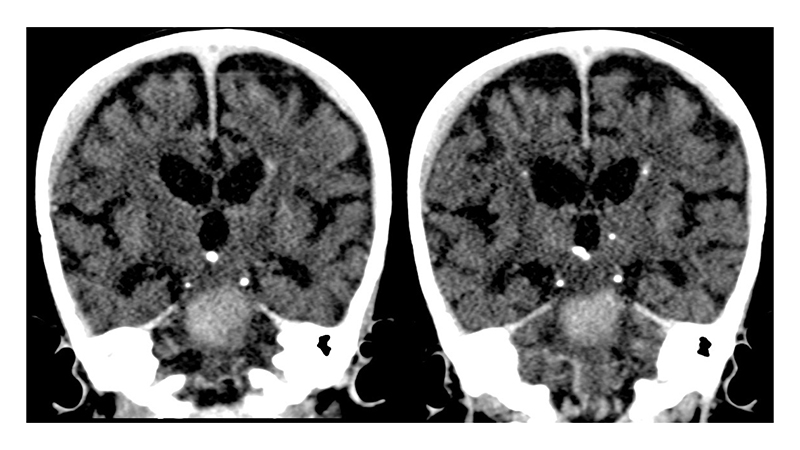

- ενώ φαίνονται και αμφοτερόπλευρα υποσκληρίδια αιματώματα στην κυρτότητα των ημισφαιρίων, κυρίως δεξιά,

- παρομοίως υποφλοιώδεις και υποεπενδυματικές μικροαποτιτανώσεις υπερσκηνιδιακά και υποσκληρίδια αιματώματα.